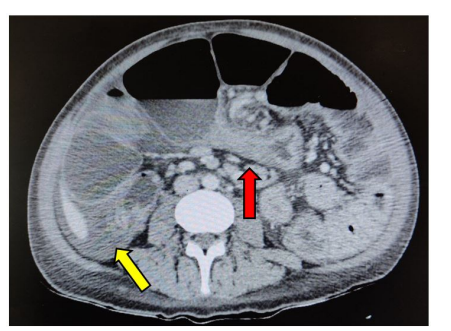

A CT scan of the abdomen and pelvis with intravenous contrast was done and revealed the presence of multiple dilated small bowel loops, with a diameter reaching about 8cm, multiple air fluid levels, fluid in the Douglas pouch and a clear transitional zone in the distal ileum before the ileocecal valve (Figure 1). Given his clinical condition and imaging findings, the surgery team decided to operate on the patient. Therefore, a laparotomy was performed.During the surgery, fluid was encountered in the pelvic region which was aspirated and sent for culture studies. Intraoperative findings revealed remarkable small bowel distension reaching up to 10cm in diameter (Figure 2). The distension extended along the entire length of the ileum. A very large ileosigmoidal fistula measuring 5cm in length and 0.5cm in diameter was detected along the distended small bowel 15 cm from the ileocecal valve. A stricture measuring about 8cm in length, representing the transitional zone seen on imaging, existed 5 cm proximal to the ileocecal valve. The fistula was emerging from the stenosed bowel segment.